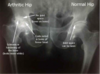

Osteoartrose (slidgigt) (også bare kaldt artrose): **Forekomst**: den hyppigst forekommende ledsygdom Lokalisation: **1** **Symptomer og Kliniske fund**: **2** **Rtg. bækken**: afsmalnet ledspalte (brusken reduceret), subkondral sklerosering (kompakt knogle), osteofytter, subkondrale cyster, deformering Behandling: primært symptomatisk behandling

1: hyppigst i hofteleddet 2: * Belastningsrelaterede smerter * Evt. smertetriade (igangsætningssmerter, lindring ved bevægelse og forværring ved øget belastning)